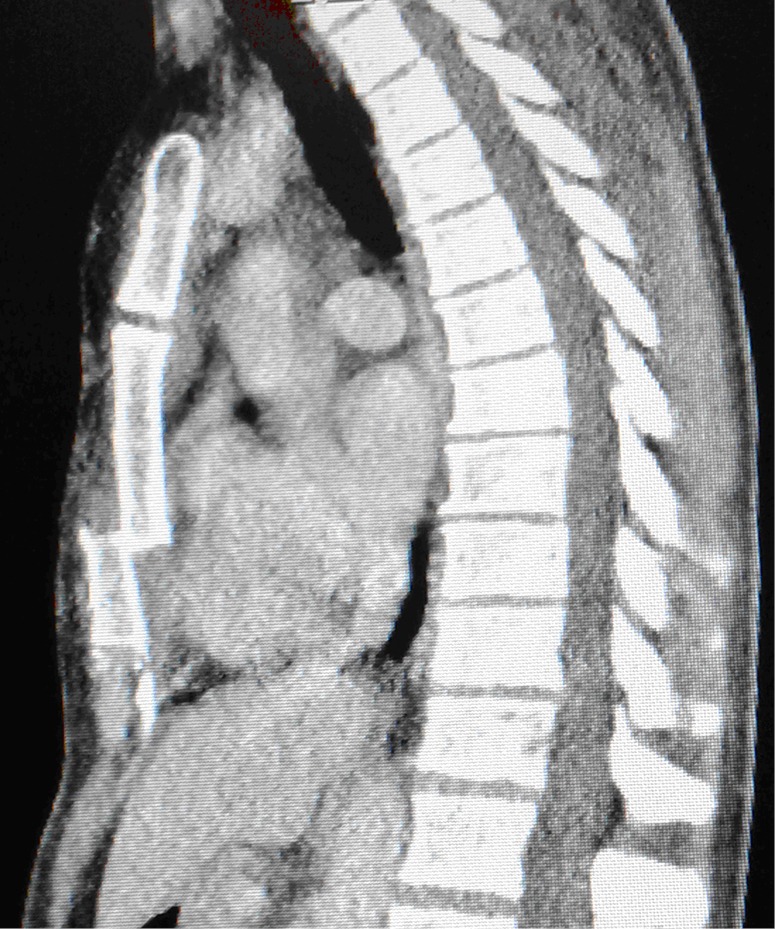

Figure 1.

Preoperative CT scanning revealed dislocation and overlapping fracture components.